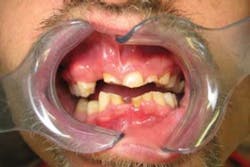

This is an article about one of those people. His name is Happy, though the name was decidedly misleading. He had been coming to me for years and his visits consisted of emergency extractions, root canals, and fillings.

Due to financial considerations, he had not been able to complete any treatment with permanent restorations, and his teeth were, quite simply, breaking down and wearing out.

Happy is a young man working hard to get his life going in the right direction. He took odd jobs, but could never make the financial commitment necessary to take proper care of his teeth. I repeatedly warned him that his teeth were falling apart and his choices were decreasing, but each year he continued to neglect them. In short, he simply could not afford to worry about his looks.

I explained to him it was a cosmetic solution and not permanent, but that he could easily reap the benefits of having a great smile without the significantly high cost of permanent crowns. To my surprise, he agreed! We chose a shade he liked (he had always wanted whiter teeth, he told me) and we took photos and made impressions.

He ordered both upper and lower Snap-On Smile arches, then took care of his payment and made his delivery appointment. I can tell you that the delivery was one unforgettable appointment for my staff, my patient, and me.